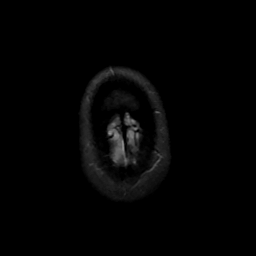

MR Study #16, June 23, 1991 -- Slice #48

[Home][Help][Clinical][Tour 1][Tour 2] Slice 48